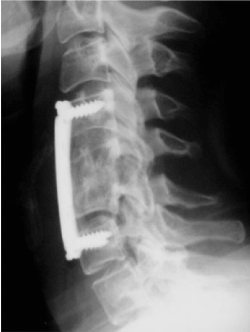

A 24-year-old man was referred to our center for evaluation of possible baroreflex failure. Her chief symptom was volatile HT and HR. Six months before admission, the patient experienced a neck trauma during a football playing accident which resulted in severe trauma to the cervical spine C5 (Figure 1). He Undergoes surgical reparation of his cervical spinal (Osteosynthesis C4-C6 with implantation of iliac graft) (Figure 2).